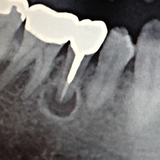

歯内療法か?外科的療法か?病理組織的には病変に上皮があれば歯根嚢胞(外科的療法必要)、上皮がなく繊維と血管だけの場合は歯根肉芽腫(歯内療法で治癒可能)と呼ばれますが、実際の所レントゲン(CTを含む)で判断するのは困難です。臨床の現場ではまず歯内療法のみを選択しますが、治癒しない場合は外科的療法(嚢胞摘出&歯根端切除術)に移行するといった流れになることが多いです。 |